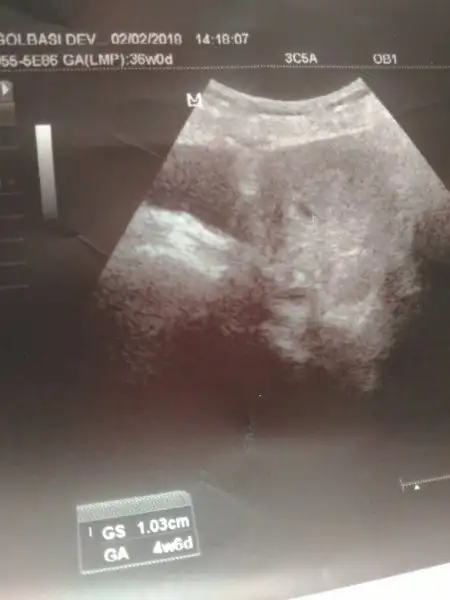

Resmini verdimi kesenin canım varsa atarmısın bi bakalımcanım acil beni rahatlatti

Cuma günü 1371 çıkınca doktor bana diyecektiki bizim üst sinirimiz bu sizin degeriniz bundan fazla kesede göründü gidin şu tarihte gelin bebeğe bakalım adam oturdu hesapladı en azından 1800 çıkmalıydı dedi 2 güne bir tekrarlayalım dedi üst limitlerinin o oldugundan haberi yok yeni geldi bu doktor ve ilk görev yeri